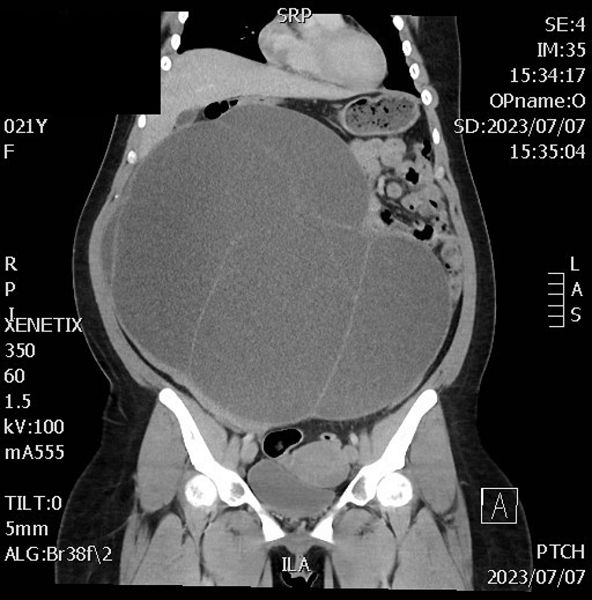

月前兩名60歲及21歲女性都因為肚子越來越大到屏基就醫,經過超音波、電腦斷層檢查發現兩位都罹患卵巢囊腫,且腫瘤已經有30公分大小,隨後進行單孔腹腔鏡手術將腫瘤切除取出,順利出院。

劉士傑指出,卵巢囊腫經常發生在20至50歲女性身上,大部分是良性的,初期沒有明顯症狀,通常是在囊腫大到壓迫周圍器官時才感覺不適,病人多半以為自己變胖成了「小腹婆」而不在意;或感覺肚子脹脹的以為有宿便、消化不良等腸胃問題,劉主任建議女性朋友定期進行健康檢查,檢查項目除了婦科超音波外;也抽血檢驗卵巢癌指標如Ca-125,Ca-199, B-HCG等,以期及早發現婦科腫瘤。